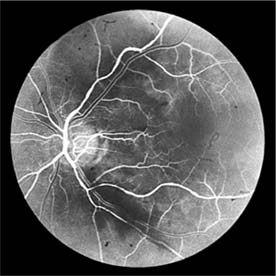

The appearance of the fundus in hypertensive retinopathy is determined by the degree of elevation of the blood pressure and the state of the retinal arterioles. Thus, in young patients with accelerated hypertension, an extensive retinopathy is seen, with hemorrhages, retinal infarcts (cotton-wool spots), choroidal infarcts (Elschnig's spots), and occasionally serous detachment of the retina (Figure 15-10). Severe disk edema is a prominent feature. Vision may be impaired but is restored if blood pressure is reduced with caution.

Figure 15-10

Figure 15-10: Accelerated hypertension. Fluorescein angiogram in a young man showing arteriolar constriction, dilation of capillaries with microaneurysms, and areas of closure. Marked disk edema is present.

In contrast, elderly patients with arteriosclerotic vessels are unable to respond in this manner, and their vessels are thus protected by the arteriosclerosis. It is for this reason that elderly patients seldom exhibit florid hypertensive retinopathy (Figure 15-11).

Figure 15-11

Figure 15-11: Accelerated hypertension. Fluorescein angiogram in an elderly wom.an showing marked arteriolar constriction and irregularity but few signs of florid retinopathy.

Fluorescein angiography has made possible accurate documentation of these microcirculatory changes. In young patients with hypertension, arteriolar attenuation and occlusion are seen, and capillary nonperfusion can be verified in relation to a cotton-wool spot, which is surrounded by abnormal dilated capillaries and microaneurysms with increased permeability on fluorescein angiography.

Resolution of the cotton-wool spots and the arteriolar changes occurs with successful hypotensive therapy. In elderly patients, the underlying arteriosclerotic changes are irreversible.